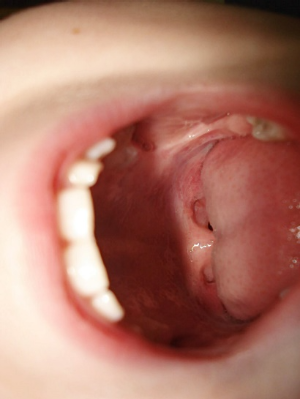

입냄새 제거에 필요한 또 다른 방법은 '혀 닦기'입니다. 혀에는 백태라 불리는 흰색의 설태가 쉽게 쌓이며, 이는 세균과 음식물 잔해로 구성되어 분해되면서 불쾌한 냄새를 내게 됩니다. 이를 제거하기 위해 혀 스크레이퍼를 사용해 혀에 축적된 박테리아와 점액층을 부드럽게 제거하는 것이 효과적입니다. 혀 뒷부분에서 시작해 앞으로 부드럽게 긁어내는 것이 좋습니다. 만약 혀 스크레이퍼가 없다면, 칫솔로도 혀를 깨끗이 닦을 수 있습니다. 혀 청소는 입냄새 관리의 중요한 부분이므로 잊지 말고 실천해야 합니다.

4. 편도결석 치료

편도염은 주로 항생제와 진통제 등의 약물 치료로 관리되며, 반복되거나 심각할 경우 편도 제거 수술을 고려할 수 있습니다. 방법은 결석을 압출하거나 레이저로 편도음와를 줄이는 방법 등이 있습니다.

편도결석은 음식물 찌꺼기와 세균이 뭉쳐 편도 표면에 낀 작은 알갱이입니다. 이로 인해 입냄새가 심해지고, 목에 이물감을 느낄 수 있습니다. 편도결석은 일반적으로 편도염을 제대로 치료하지 않아 발생하며, 입안 청결 유지, 수분 섭취 등이 예방에 중요합니다.